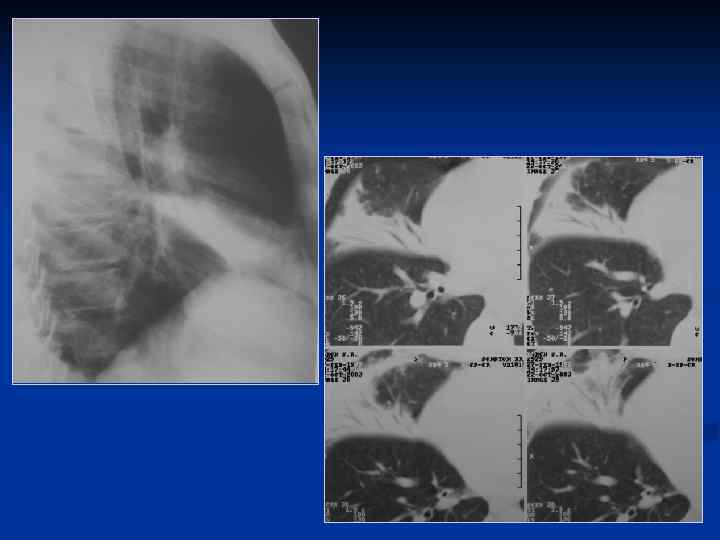

1 ПН аксиллярного сегмента. Провисание косой междолевой плевры - выпот